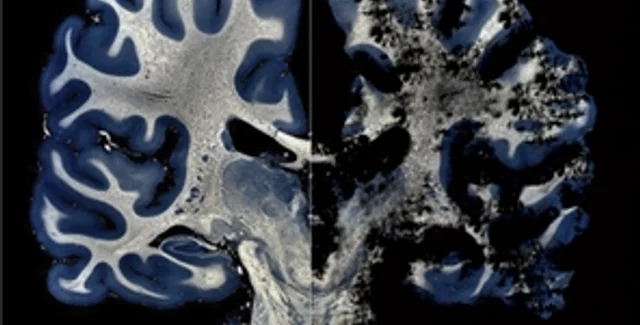

Морг. Патологоанатом вскрывает череп человека, который еще вчера был жив. Однако врачи так и не смогли с уверенностью поставить ему диагноз. В последнее время несчастный никого не узнавал, его голова и конечности непроизвольно тряслись. Посмертное исследование позволило установить: необратимые изменения в мозге больного вызвали прионы.

— Прионы, или патогенные белки, ведут к фатальным изменениям головного мозга, — рассказывает заведующий лабораторией биохимии Института отоларингологии АМН Украины им. Коломийченко, кандидат биологических наук Сергей Веревка. — Их открыл профессор неврологии, вирусологии и биохимии Калифорнийского университета Стенли Прузинер, за что получил в 1997-м Нобелевскую премию. Прионы вырабатываются клетками центральной нервной системы, то есть имеются абсолютно у всех млекопитающих, в том числе и у нас с вами. нормальные прионы могут мутировать в патологическую форму. Отличие ее от нормальной — в укладке белковой цепи. Две химически идентичные белковые молекулы в зависимости от способа скручивания "молекулярного клубка" ведут себя абсолютно по-разному — либо быстро расщепляются ферментами по выполнении своих функций, либо вызывают необратимую и ведущую к смерти деградацию клеток центральной нервной системы.

— Особенно плохо изучены наследственные прионные болезни, — отмечает Руфина Виноградова. — У них длительный скрытый период развития — около 20 лет. Человек может годами быть носителем прионной инфекции и не знать об этом. Обычно ее определяют уже после того, как он заболел, а то и умер.

Но как быть с донецкими трупами? Свидетельствуют ли они, что нам угрожает реальная, а не выдуманная опасность прионной болезни? Профессор Шлопов утверждает, что у умерших людей была обнаружена спорадическая (от греч. sporadikоs — единичный, отдельный) форма патогенных прионов, никак не связанная ни с инфицированным мясом, ни с переливанием крови. К тому же, отмечает ученый, прионы были найдены не одномоментно у нескольких покойников, а на протяжении нескольких лет.

— Первоначально причиной их смерти прионная болезнь не считалась, — объясняет г-Шлопов. — Истинный фактор выяснился, когда мы с коллегами ретроспективно изучали морфологические и клинические признаки их болезней. Разумеется, это наше исследование — сугубо научное. Смерти никак не связаны с употреблением в пищу инфицированного мяса или с переливанием крови.